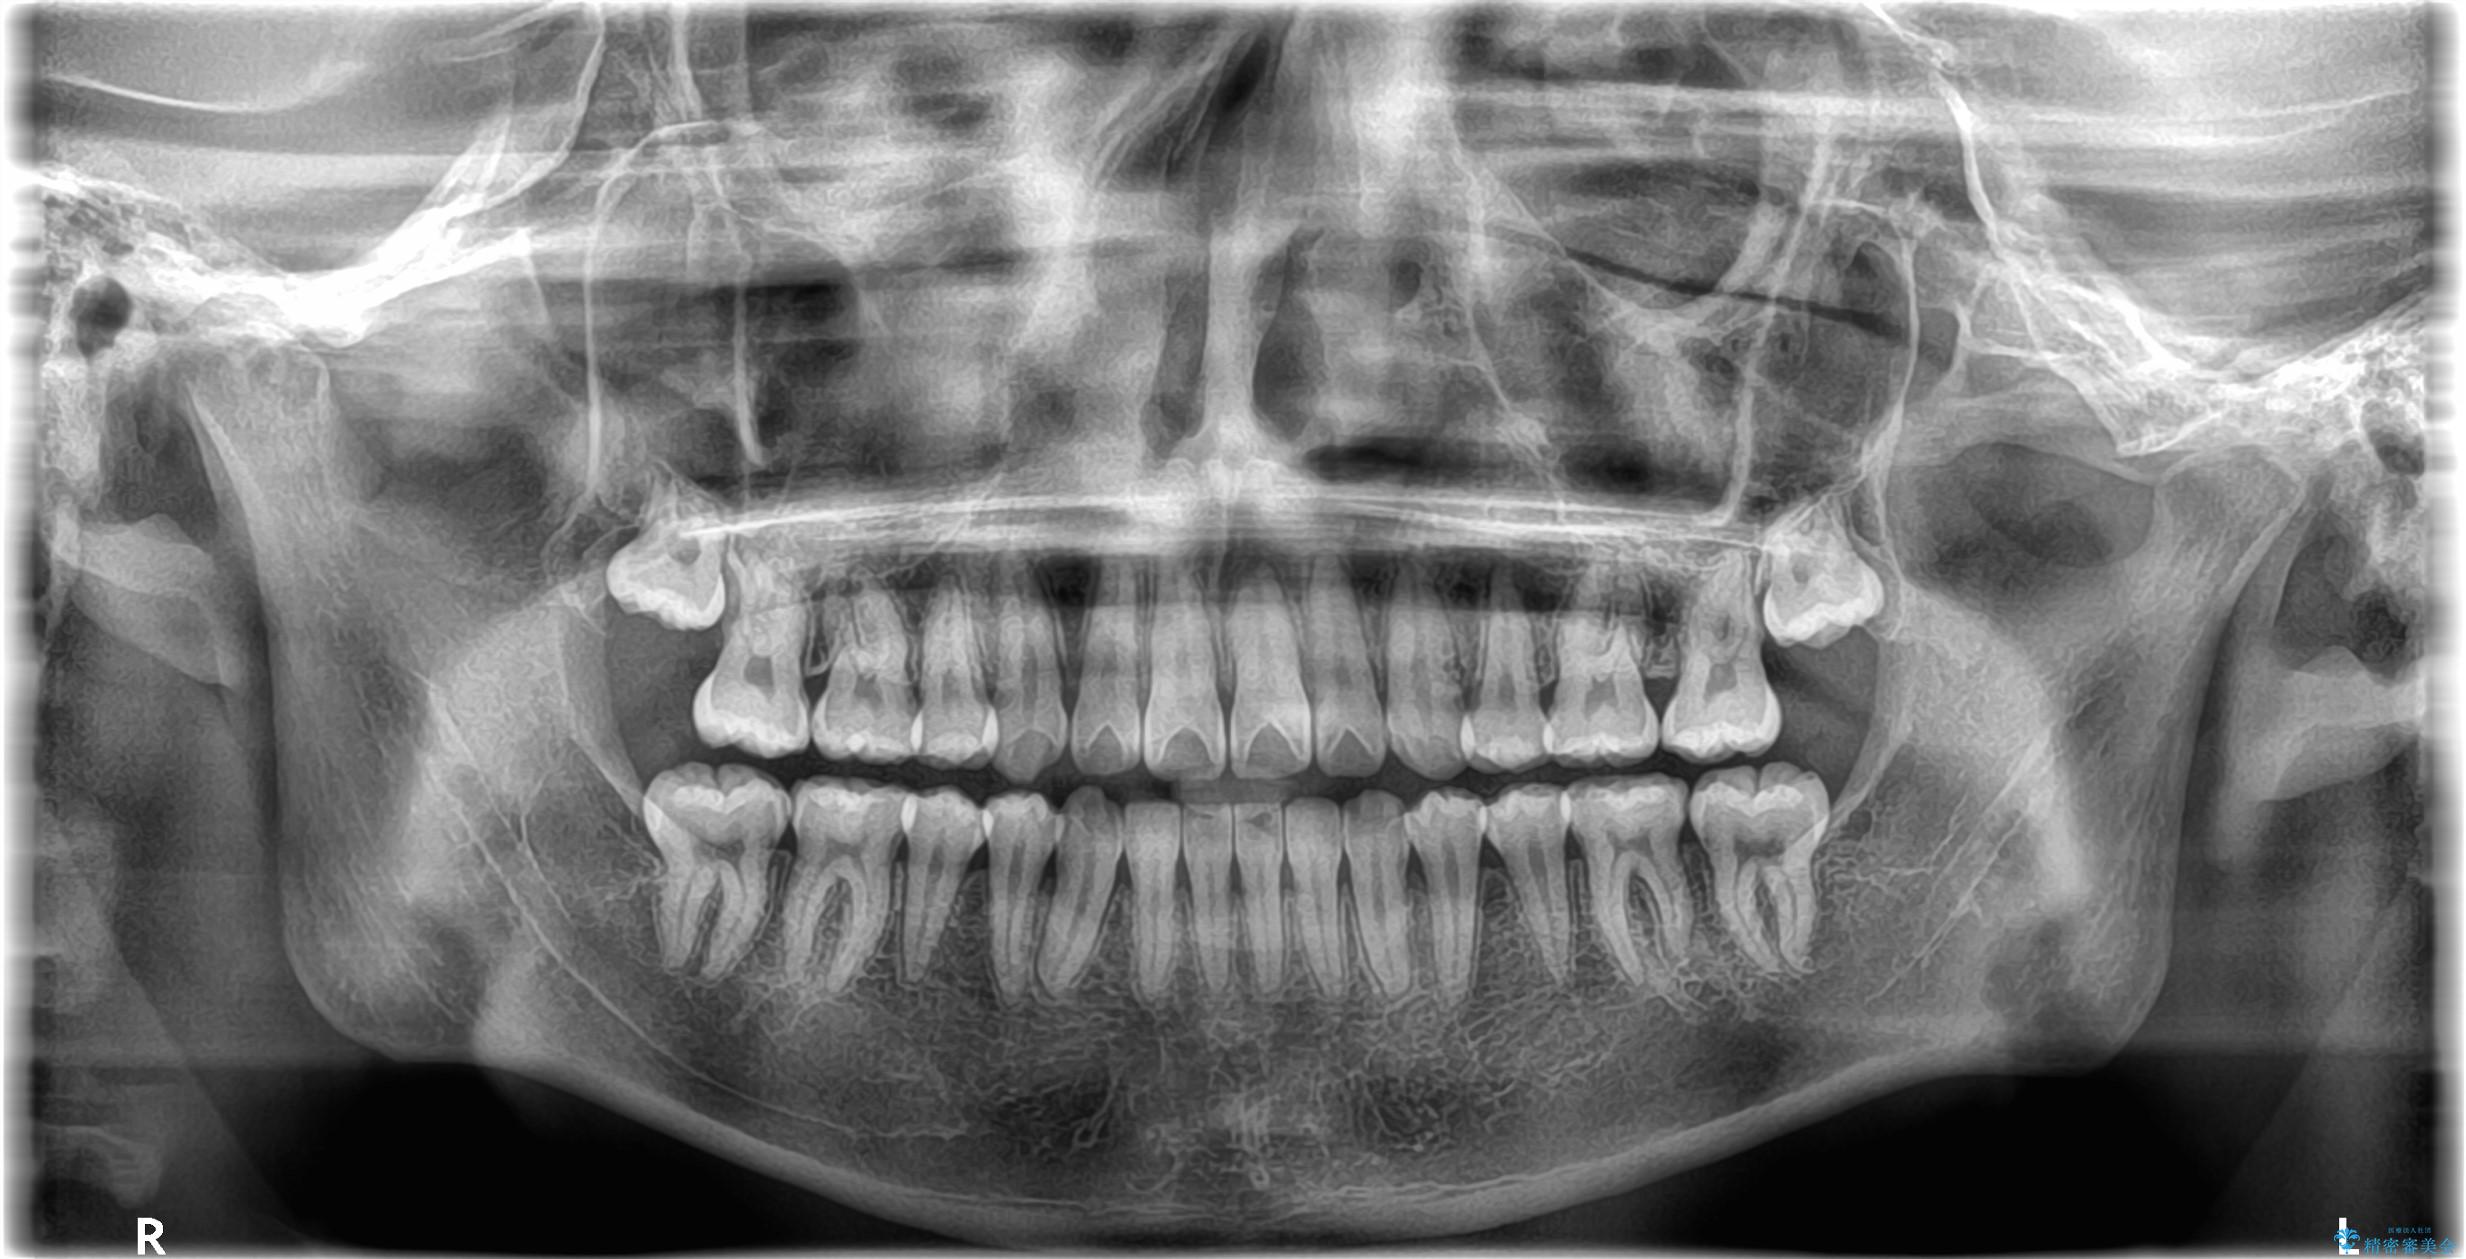

矯正の精密検査の結果上顎左右4番の計2本を抜歯し、審美性に配慮したワイヤー矯正装置(審美装置)を用いて治療を行いました。

八重歯などの歯列のデコボコが綺麗に改善され、患者様にも大変喜んでいただけました。また、咬み合わせが深い「ディープバイト」も併せて改善し、見た目だけでなく機能面でもバランスの取れた咬合を獲得しています。